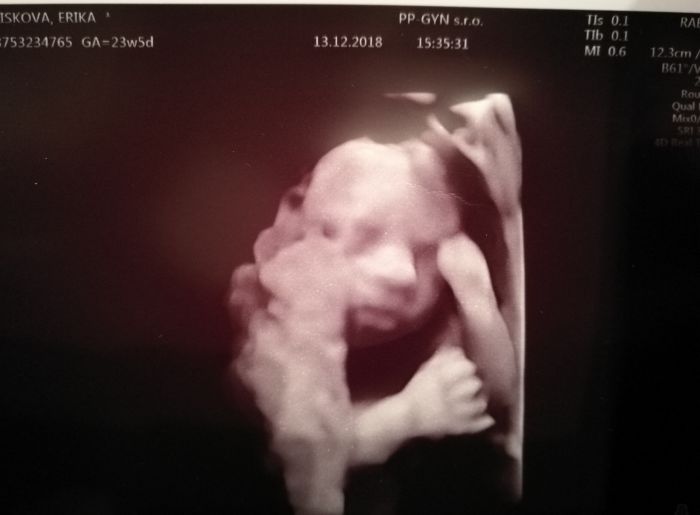

My dnes byli na tom 3d, tak holcicka je to stoprocentne a je vazne prekrasna, jsem z ni uplne posrandena, pusinka moje malinka.

Eriko gratuluji, krásná fotka

Market, bude to Hanicka, kocarek mame z druhe ruky, ale je uzasny a vypada jako novy, mame Jane Slalom, momentalne zaparkovany u tchanu.

Jinak zatim nic moc nachystano nemam, postylku budu objednavat v lednu a od unora uz chci zkoncit v praci, tak se postupne vrhnu na zbytek. Zatim jsme v malem byte, tak to stejne nemuzu prehanet. Termin mam 6.4., tak uvidim kdy se male bude chtit ven, vcera nam rekl, ze ma pres 600g a podle jeho sona vyjel termin 4.4..